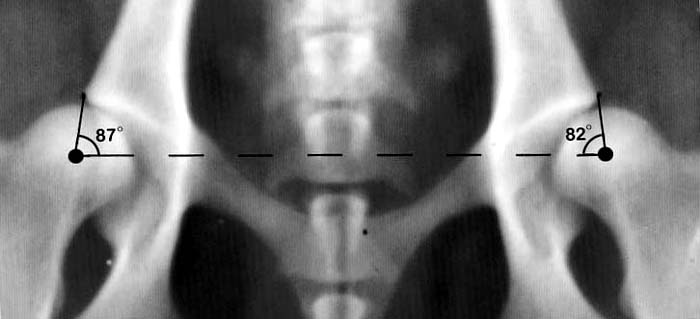

Η διάγνωση γίνεται με συνδυασμό των συμπτωμάτων, των ευρημάτων της κλινικής εξέτασης από τον κτηνίατρο και της ακτινολογικής εξέτασης. Η οριστική διάγνωση δεν είναι πάντα εφικτή. Τα παραπάνω μέσα, παρόλα αυτά αποτελούν έναν πολύ καλό οδηγό για την εκτίμηση της κατάστασης του ζώου.